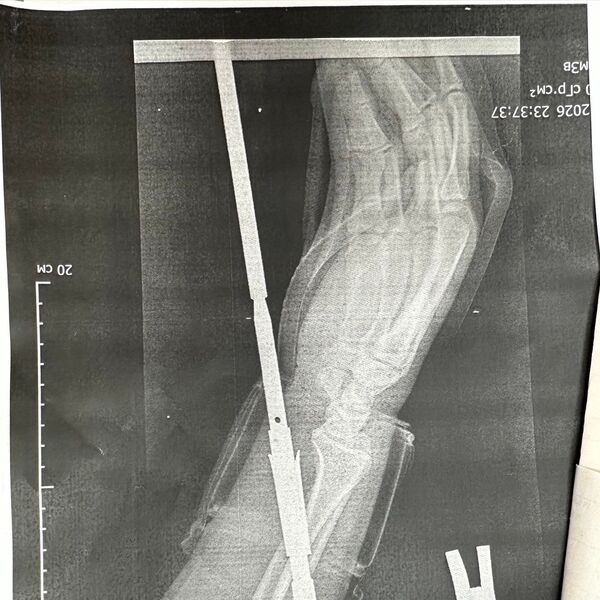

«Гарпун с двумя зубцами прошел между костями, не задев их. Специалисты извлекли инородное тело, обработали колотую рану и оказали пациенту квалифицированную помощь», — говорится в публикации.